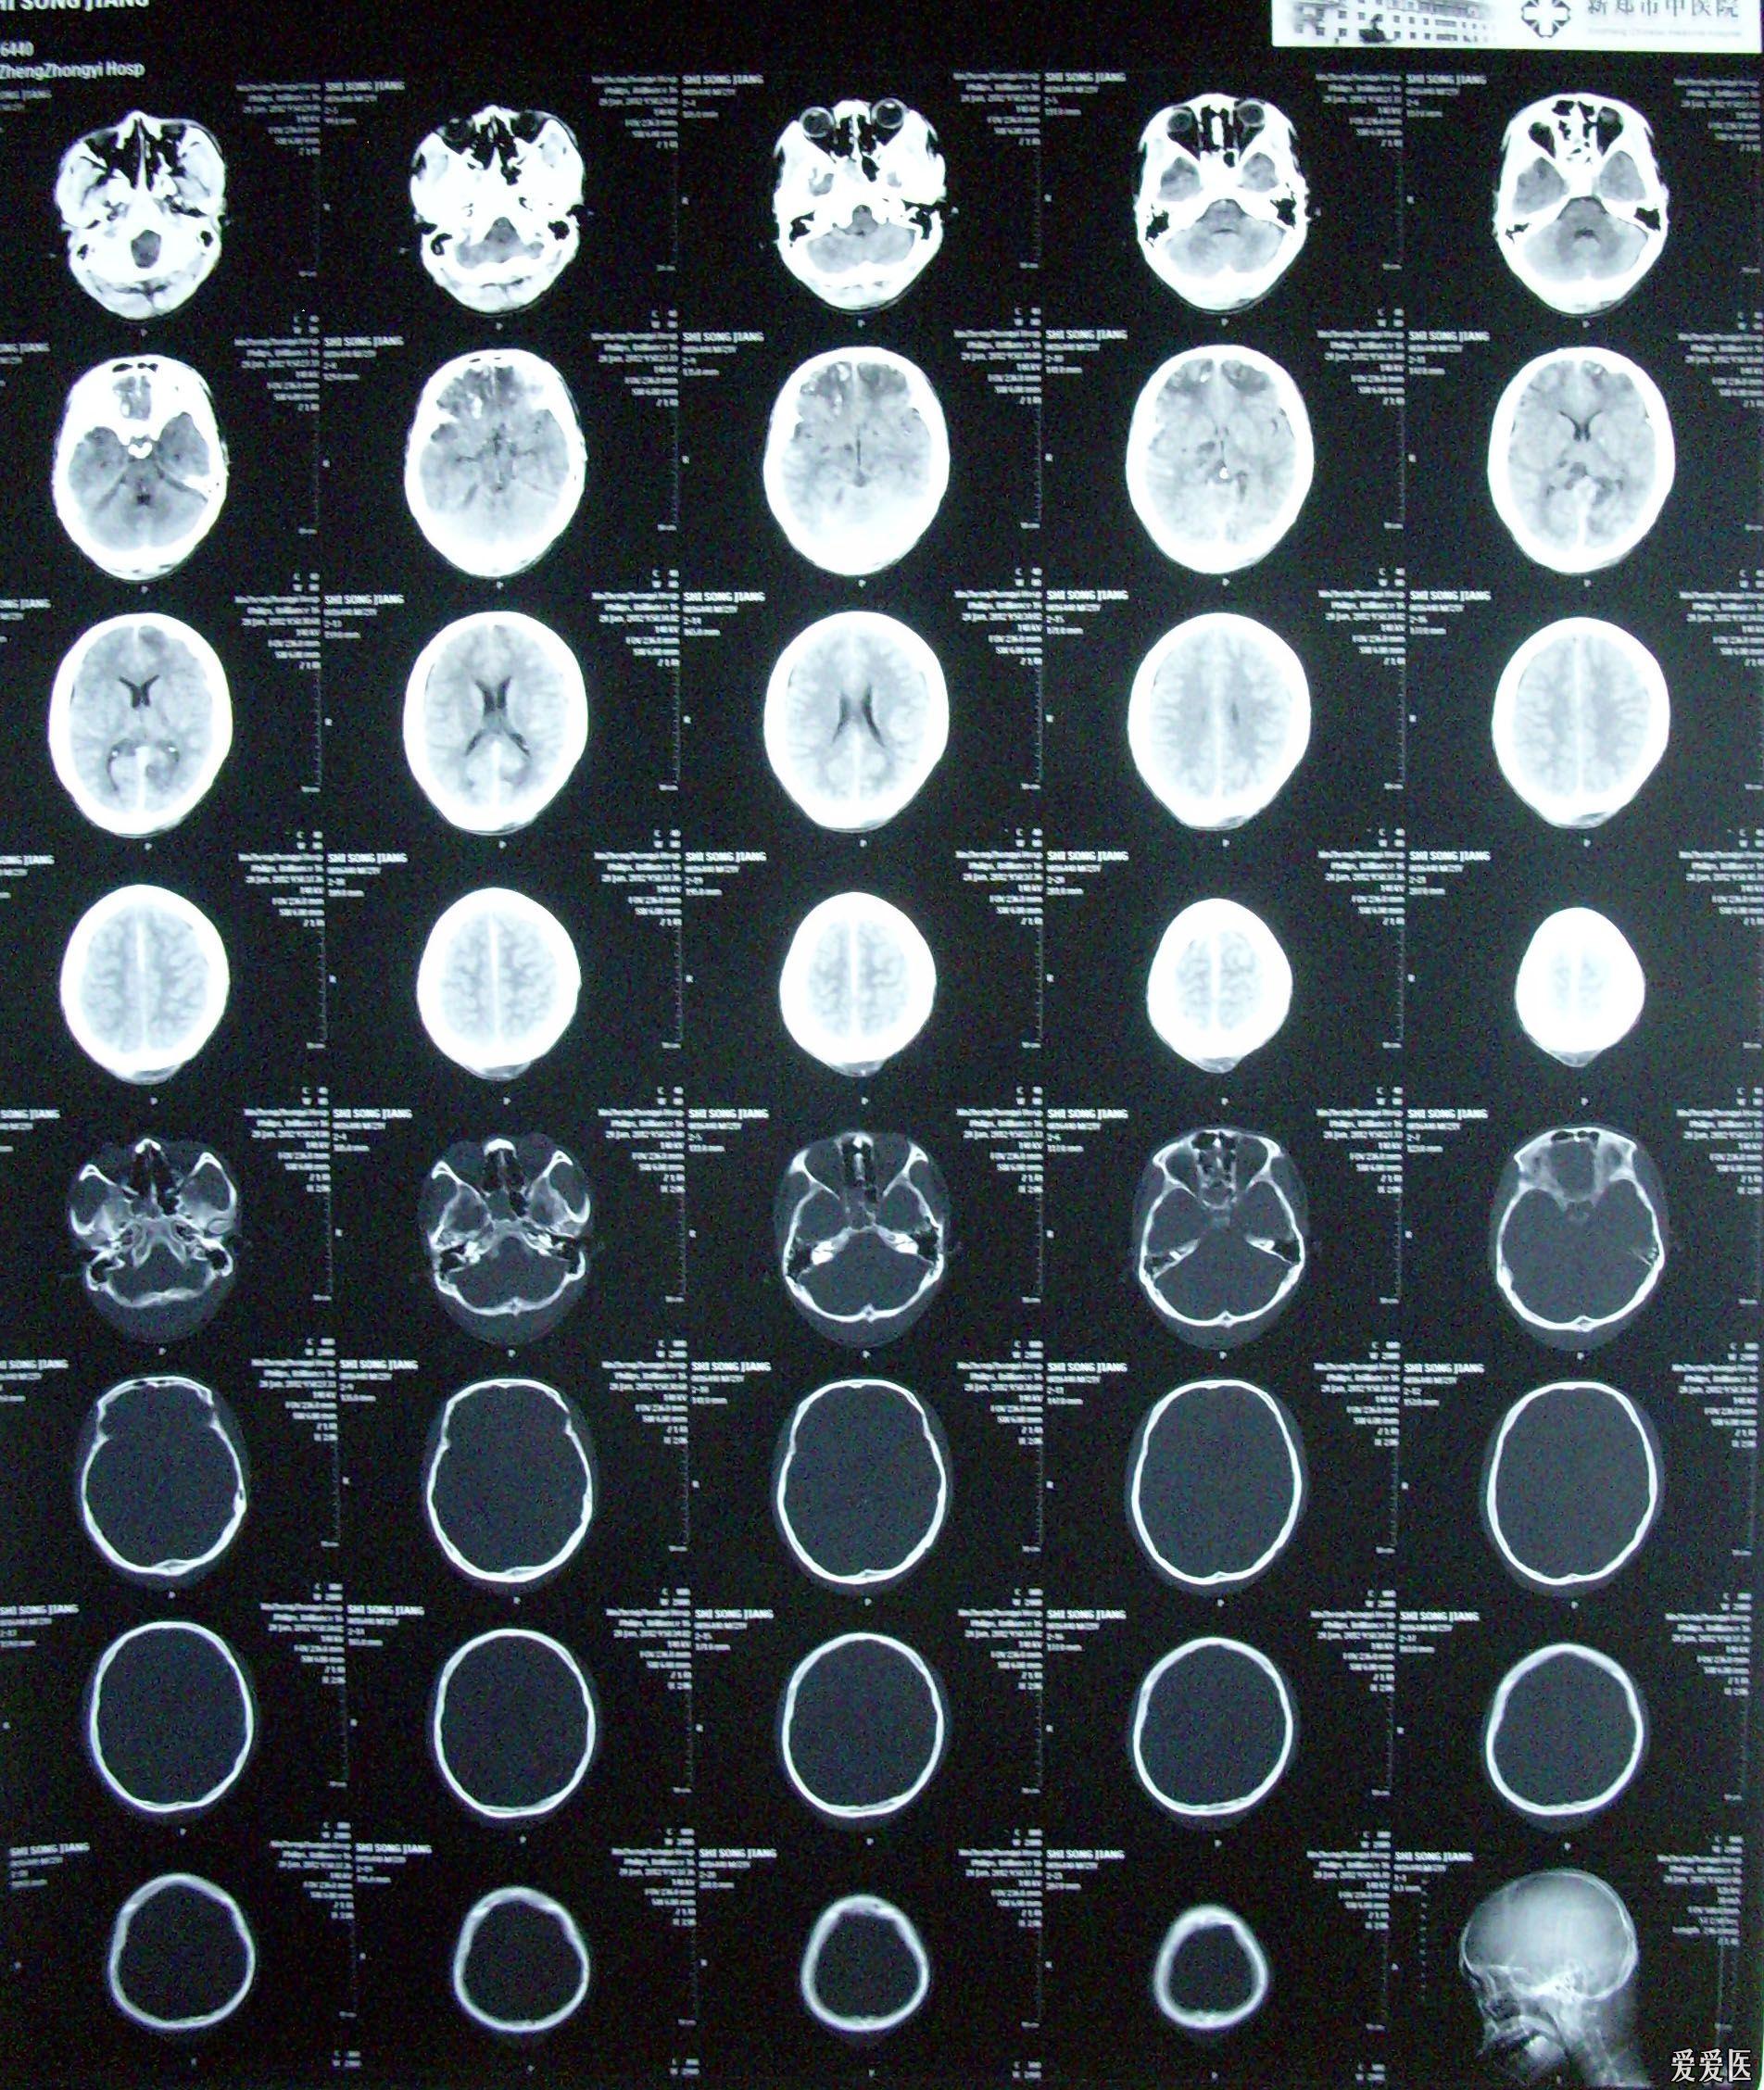

重型颅脑损伤一例

图片尺寸1920x2428